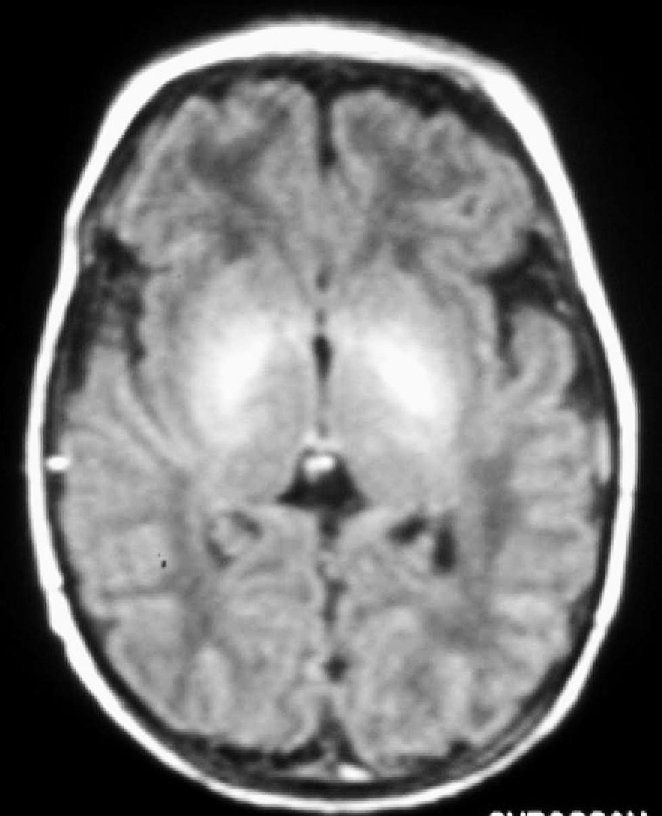

Fig. 1.Resonancia magnética.Secuencia T1 en plano axial. Hiperintensidad de señal que de forma simétrica afecta a núcleos palidales y subtalámicos.

A las 48 horas de su ingreso presenta una crisis de hipertonía, motivo por el que se realiza una resonancia magnética.